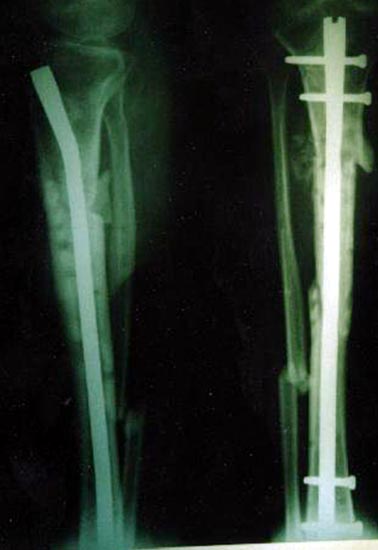

病例三、患者男性,25岁,胫骨下段骨不连3年

图3 病例三、患者男性,25岁,胫骨下段骨不连3年。我们用异体骨板提供支撑力,植如患者自体骨髓细胞经与松质骨和骨生长因子复合物,骨折在9个月后愈合。